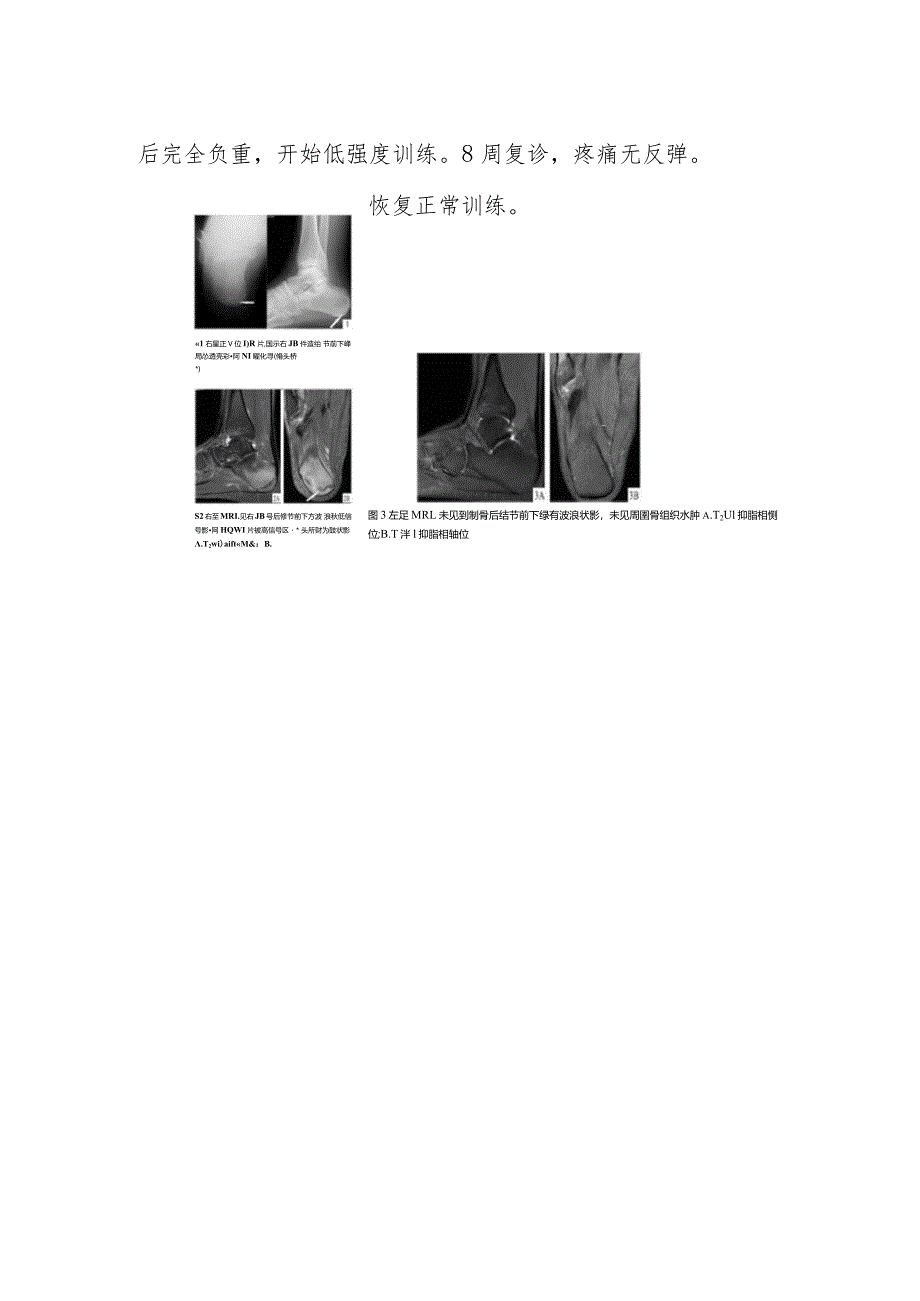

1、骨科单侧跟骨疲劳骨折病例分析专题报告临床资料患者,男,19岁,新兵。正步训练后出现右足跟痛不适4周。来诊前6周开始正步训练,间断长跑;训练1周后出现右足跟部隐痛,休息后消失,晨起明显;4周前疼痛变为持续性,随站立及行走时间延长加重,影响正步训练,外敷膏药无效。2016年11月25日来诊。查体:跛行入诊室,右跟骨后结节周围压痛,内侧明显,疼痛VAS评分7分,内侧轻度肿胀,跟骨DR片报告未提及异常。但读片发现跟骨后结节前下缘偏内侧局部密度增高区及线样透亮影,见图1。怀疑跟骨疲劳骨折,因不能确切诊断,行MRl检查。影像报告:胫骨远端、距骨及跟骨斑片状低TlWl及长T2WI信号,提示胫骨、距骨及跟骨多

2、发骨挫伤。但阅读MRl发现,跟骨后结节前下方尚可见波浪状TlWl及T2WI低信号影,见图2。讨论在未能明确诊断前,先给予右小腿石膏制动并避免右下肢负重。然后行对侧MRl检查,未见左跟骨骨质异常及波浪状影,见图3。确诊右跟骨后结节骨挫伤并疲劳骨折,Fredericson分级为4b级。患者石膏固定4周后右跟骨痛消失。拆除石膏,部分负重扶拐行走,逐渐增加,2周后完全负重,开始低强度训练。8周复诊,疼痛无反弹。恢复正常训练。1右星正V位I)R片,国示右JB件造绐 节前下峰局怂透亮彩阿NI曜化寻(脩头桥*)S2右至MRI.见右JB号后修节前下方波 浪秋低信号影网HQWI片被高信号区* 头所财为鼓状影.T2wi)aiftM&:B.图3左足MRL未见到制骨后结节前下绿有波浪状影,未见周圉骨组织水肿a.T2Ul抑脂相恻位;B.T泮l抑脂相轴位